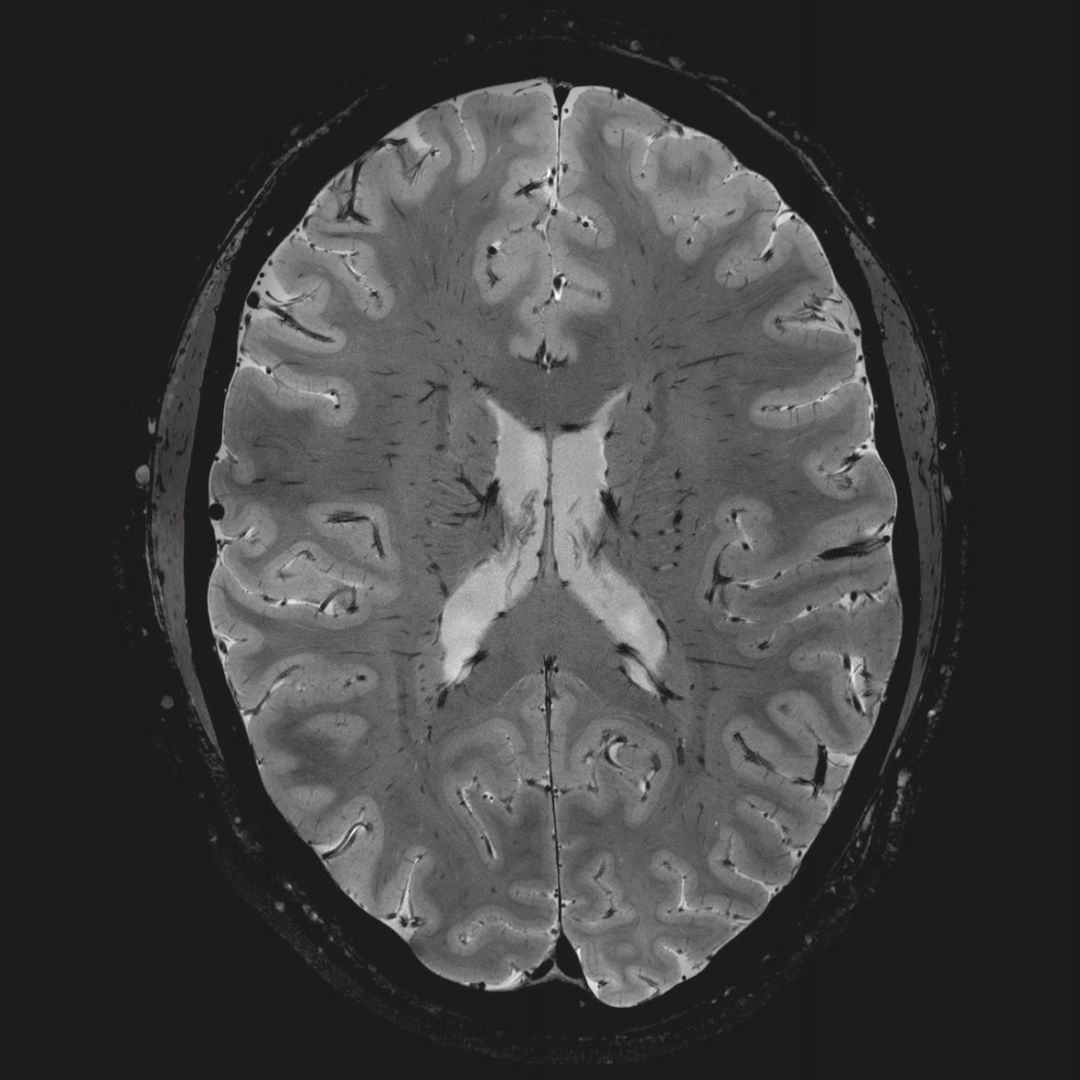

1毫米的各向同性分辨率DTI:神經(jīng)纖維束的交叉細節顯示

0.8毫米的各向同性分辨率:精確劃分灰質(zhì)和白質(zhì)

0.8毫米的各向同性分辨率:超精細的解剖細節,例:小腦的精細結構

超精細的解剖細節:T2對比

0.17 x 0.17 x 0.8毫米分辨率超高。